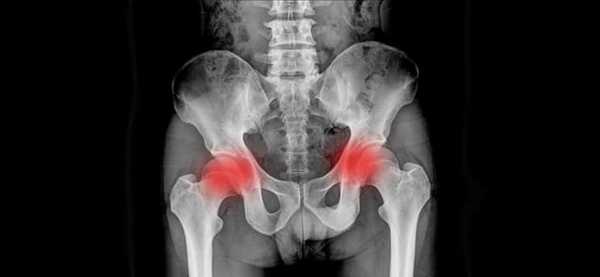

Сакроилеит - это воспаление крестцово-подвздошных суставов (сочленений). Оно может быть различной природы и затрагивать либо один из суставов (односторонний сакроилеит), либо оба (двусторонний сакроилеит).

Асептический сакроилеит может наблюдаться при многих ревматических заболеваниях, в том числе – при псориатическом артрите и болезни Рейтера. Двусторонний сакроилеит имеет особое диагностическое значение при болезни Бехтерева, поскольку рентгенологические изменения в обоих крестцово-подвздошных сочленениях в этом случае выявляются на начальных стадиях – еще до формирования сращений между позвонками. Характерная для сакроилеита рентгенологическая картина в таких случаях обеспечивает раннюю постановку диагноза и позволяет начать лечение в максимально благоприятный для этого период.

На первой стадии сакроилеита на рентгенограмме определяется умеренный субхондральный склероз и расширение суставной щели. Контуры сочленений нечеткие. На второй стадии сакроилеита субхондроз становится выраженным, суставная щель сужается, определяются единичные эрозии. На третьей формируется частичный, а на четвертой – полный анкилоз крестцово-подвздошных суставов.